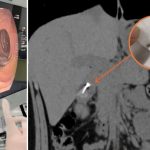

上堂“发吽哣”随时惹杀身之祸?江苏扬州一名初中男生,日前在课堂上思考问题时,竟不自觉含着圆规把玩,结果不慎吞下长达1.9厘米的锋利针头。由于初中生年纪尚轻且未有禁食,手术风险极高。幸得医护团队艺高人胆大,成功取出尖针,化解穿肠危机。

内地“荔枝新闻”报道,事发于3月31日,就读中学的小刘(化名)原本正在上堂,一时分神,竟吞下原本含在嘴里的圆规针头。大惊失色的他即告知老师,随后被送往扬州市江都人民医院急症室求医。

胃内满布残渣 手术风险极高

经过电脑扫描(CT),一条长约1.9厘米的针状异物已到达其胃部与十二指肠之间。由于针尖极为锋利,随时可能刺穿消化道,引发致命的腹膜炎。由于小刘胃内仍有大量未消化的食物,而进行全身麻醉内窥镜手术,按规定须禁食至少六小时;其次,他年纪尚轻,胃部发育未全,麻醉期间出现吸入性肺炎的风险远高于成年人。

为免尖针随着肠道蠕动造成穿孔,医疗团队决定争取时间救人。消化内科医生一面小心翼翼清理胃内残渣,一面仔细搜索。经过约40分钟,医生最终在十二指肠下段成功寻获并夹出“攞命针”。由于处理及时,小刘并未出现任何并发症,目前已无大碍。